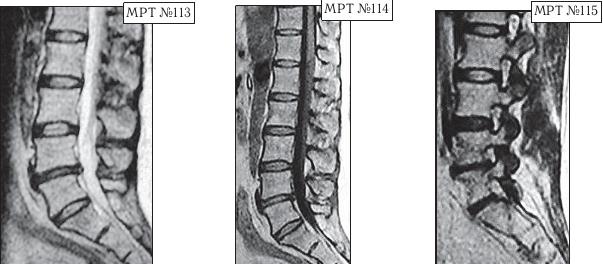

На МРТ № 108 состояние шейного отдела позвоночника пациента через 11 месяцев после дискэктомии с межтеловым спондилодезом в сегменте СIV—СV Наблюдается постхирургическая травма спинного мозга на данном уровне хирургической фрезой, кифозирование физиологического лордоза, стеноз позвоночного канала с блоком ликворных путей. На МРТ № 109 состояние шейного отдела позвоночника того же пациента через 23 месяца после дискэктомии с межтеловым спондилодезом в сегменте CIV-CV Наблюдается усугубление стеноза (абсолютный стеноз), спондилолистез (смещение вышележащего позвонка по отношению к нижележащему) СII— СIII, секвестрированная грыжа межпозвонкового диска CV—CVI. На данных снимках наглядно отображается, как подобные операции усугубляют биомеханические нарушения и тем самым способствуют развитию дегенеративно-дистрофического процесса в других сегментах позвоночника. Во время операции грыжу межпозвонкового диска в данном сегменте убрали. Но причины, которые как раз и спровоцировали образование грыжи, а именно биомеханические нарушения (дегенерация выше- и нижележащих межпозвонковых дисков, стеноз, кифоз), как были, так и остались! Несмотря на то что отдалённые последствия этой операции легко прогнозировались и полученный результат, как факт, абсолютно закономерен, подобные операции, к сожалению, как делались, так и делаются и, пожалуй, самое печальное, что и будут делаться дальше. Случаи послеоперационных рецидивов грыж межпозвонкового диска бывают разные, но причины, как правило, идентичны. Вот одна из типичных ситуаций. Врачи во главе с хирургом после хирургической операции пациента по поводу грыжи межпозвонкового диска в сегменте LV-SI в качестве профилактики посоветовали ему заниматься вытяжением позвоночника под собственным весом и укреплением мышечного корсета путём выполнения специальных упражнений на наклонной плоскости. Результат усердия пациента, последовавшего такому совету, можно наблюдать на МРТ № 110 (см. стр. 286). Исходя из анатомического и физиологического строения позвоночника человека и неизбежного действия законов физики, результат от такой «профилактики» вполне прогнозируем. Поэтому логично предположить, что врачи, посоветовавшие данному пациенту такую «профилактику», спровоцировавшую секвестрированную грыжу межпозвонкового диска в сегменте L^ — Ly, просто не знали о её последствиях. Если бы здоровье пациента позволило бы продолжить эти упражнения, то аналогичные осложнения неизбежно образовались бы и в вышележащих позвоночнодвигательных сегментах. ![]() На МРТ № 110 наблюдается состояние поясничного отдела позвоночника: секвестрированная грыжа межпозвонкового диска в сегменте LIV-LV с разрывом задней продольной связки, абсолютный стеноз спинномозгового канала. Но не спешите обвинять хирургов. Как бы это странно не звучало, это не их вина — они всего лишь удаляют часть ткани организма (грыжу). Ведь профессия хирурга заключается в знании и умении оказать пациенту своевременную хирургическую помощь, а вот послеоперационным восстановлением и «профилактикой» должны заниматься врачи-реабилитологи. Даже самые лучшие хирурги в мире, в совершенстве владеющие своей специальностью, за пределами операционной становятся обыкновенными людьми, которым, как и многим, свойственен относительный процесс познания. Требовать от них большего, это значит требовать от человека абсолютного процесса познания. Если вы считаете, что на это способен любой человек, попробуйте начать с себя. Гораздо хуже, когда врачи-реабилитологи в качестве «профилактики» дают такие «советы», вот это уже можно назвать профессиональной безграмотностью. Вот ещё случаи послеоперационных рецидивов грыж — естественной реакции организма, когда проблема решается однобоко — всего лишь с помощью хирургической операции в поражённом сегменте без общего восстановления биомеханики позвоночника.